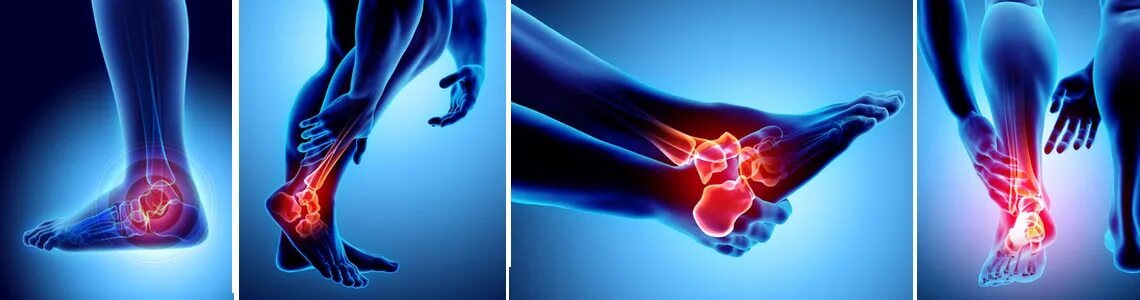

Ахиллобурсит мкб 10 у взрослых